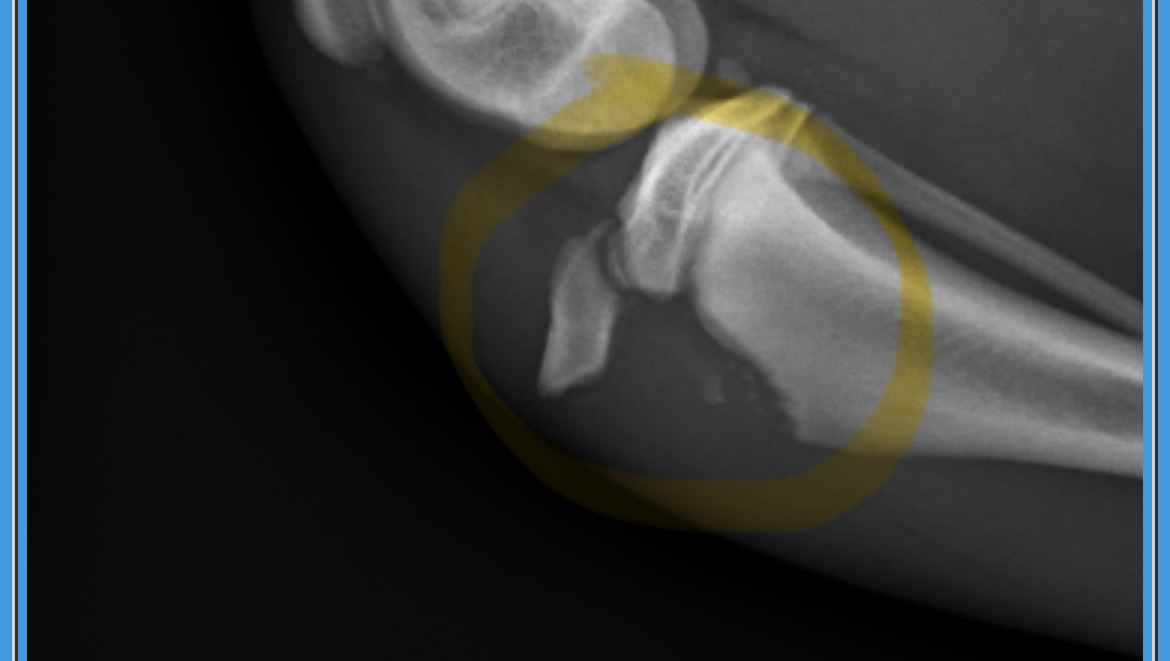

On 2/28, Luna decided to run around the apartment and she started jumping around. She ended up jumping up from the floor and when she landed, she somehow landed on her rear right leg at the wrong angle. We scooped her right up and was able to calm her down as she was crying and howling in pain. Taking a look at her leg, we could see something was off - so we rushed her to Banfield Pet Hospital that morning. She was gotten in, and was there for the bulk of the day. They had several x-rays done, and had to sedate her and give her medication for her pain. The outcome of the visit is that sadly, Luna has to have surgery. The diagnosis is a Tibal Tuberosity Avulsion/fracture.